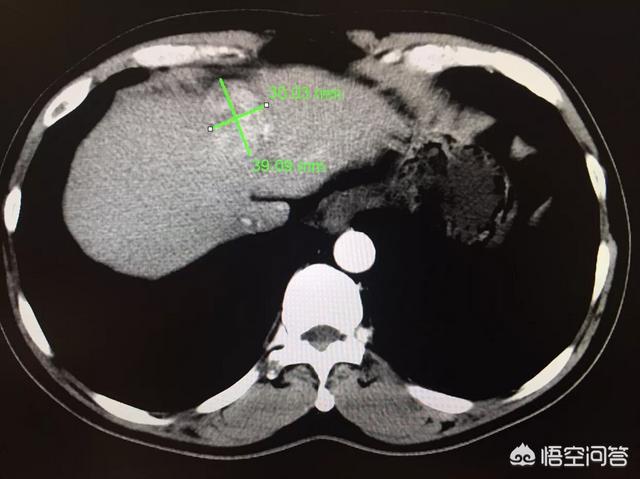

この症例は55歳の慢性B型肝炎患者である。健康診断の超音波検査で肝占有、AFP上昇、画像検査でごく典型的な肝癌を認めた。B型肝炎に罹患している場合は、定期的な検診を受けることが重要です!

CTでは、典型的な肝細胞癌が写っている。速いイン、速いアウトその顕在化を見るには、強化検査をしなければならない。このような結節を見れば、肝がんと診断する自信はある。また、肝細胞癌は病理学的に確定診断がなくても治療が可能な唯一の疾患であり、画像診断での典型性とB型肝炎の既往に基づいて診断される。